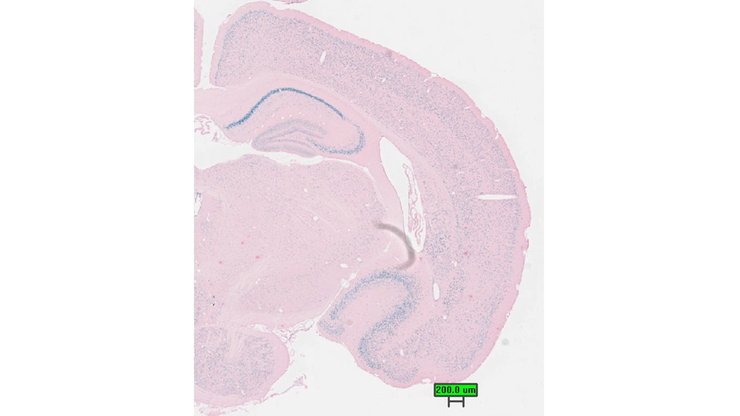

Specimen UC Davis_1866913: postnatal adult; Krit1tm1.1(KOMP)Vlcg/Krit1+ (more )

Structure Level Pattern Image Note

TS28: cerebellum Present UC Davis_1866913